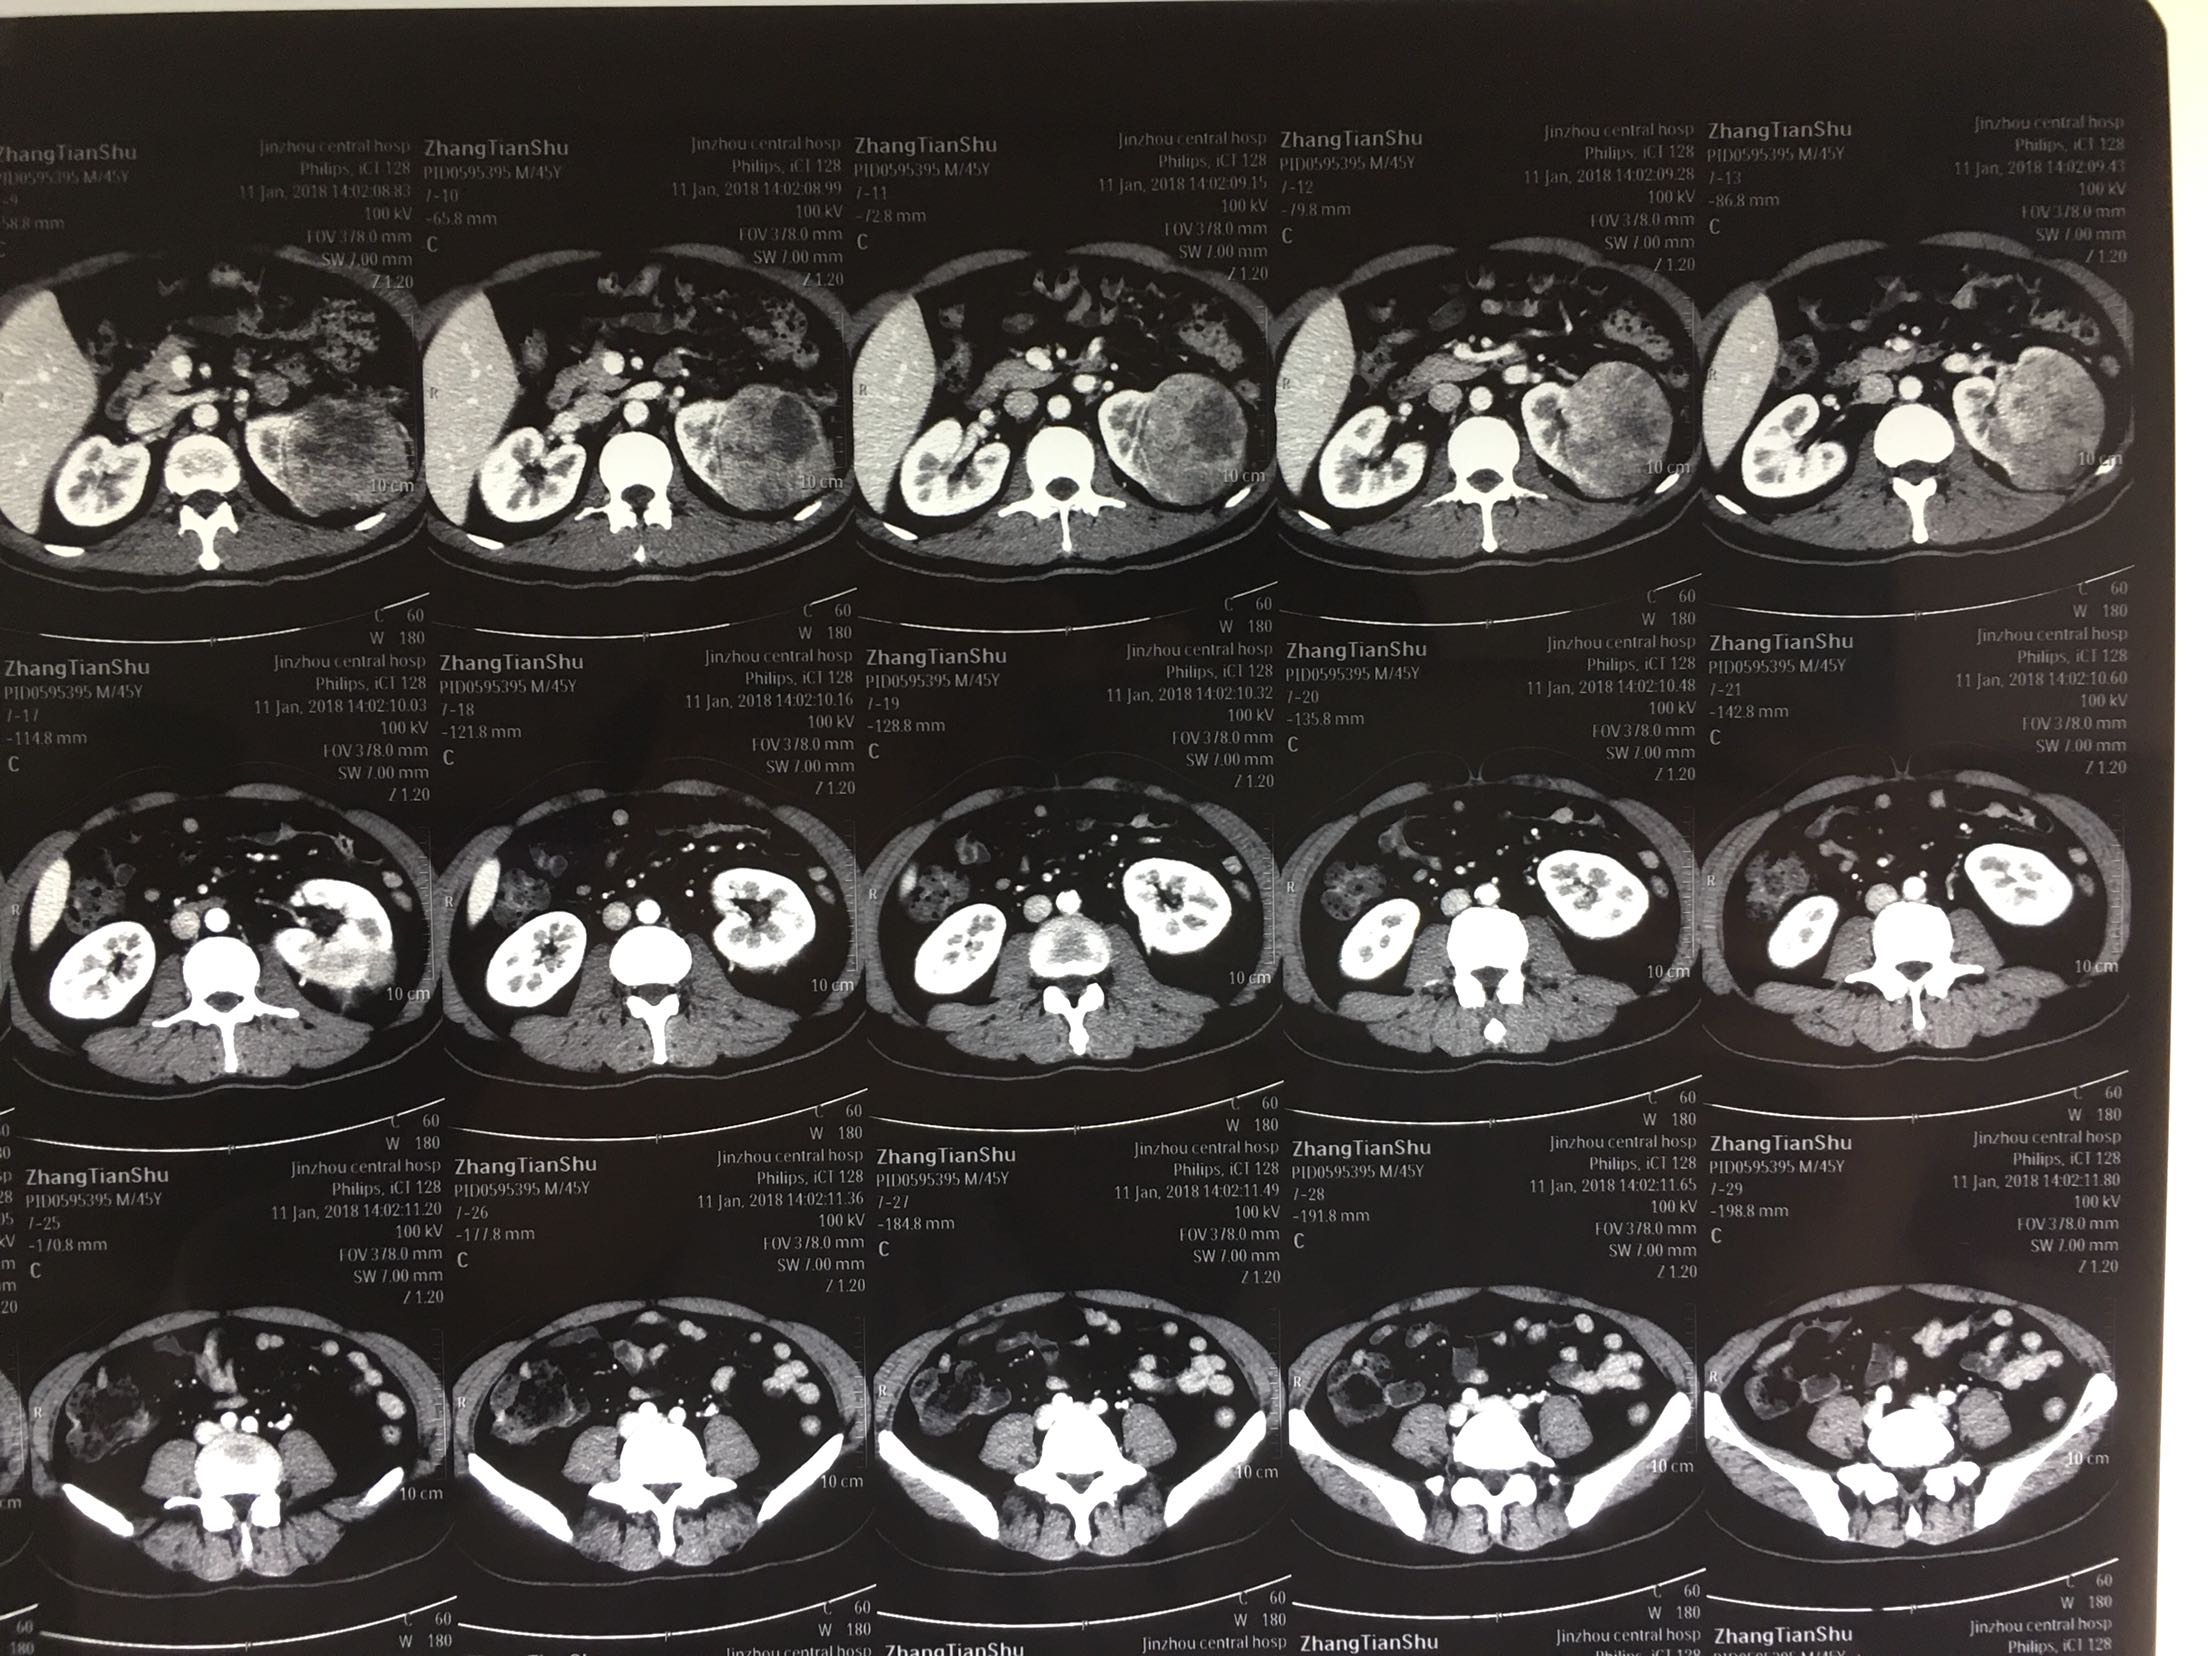

肾癌伴肾上腺转移

肾透明细胞癌 肾细胞癌

56岁男患 左腰部不适20天为主诉入院,无发热,无恶习及呕吐,无心前区不适,无尿频,无尿急,无尿痛症状。无肉眼血尿。

查体:左肾区轻叩击痛,双输尿管走形区无压痛,耻骨上区无隆起及压痛, 辅助检查:泌尿系彩超:左肾肿瘤。 ctu:左肾癌伴同侧肾上腺侵犯。

诊断:左肾癌伴肾上腺转移 治疗:根治性左肾切除术

术后病理:左肾透明细胞癌局部肉瘤样变,肾上腺及腹膜累及。 讨论:肾脏肿瘤肉眼血尿,腰疼,腹部包块为晚期肿瘤症状,预后不良。